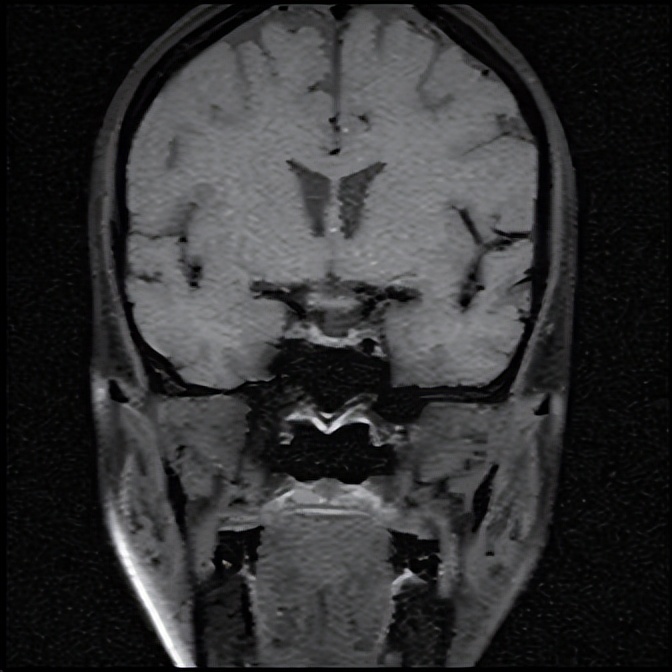

住院期间,银主任经过详细的询问病史和查体,为王女士有针对性地完善了相关检验、检查,入院急查血钠107.0mmol/L,血氯76.0mmol/L(参考范围96-108mmol/L),经积极补钠、护胃及对症支持治疗后王女士的血钠稳步上升,症状逐渐减轻,相关结果回报上午皮质醇、促肾上腺皮质激素(ACTH)水平降低,垂体磁共振未见明显异常。会不会是内分泌方面的因素导致低钠血症呢?深圳大学总医院内分泌代谢病科派驻罗城县人民医院内四科的丘雅维主治医师应邀会诊。丘医生分析患者体型消瘦,皮肤黏膜无明显色素沉着,低血压,轻度贫血,白细胞及中性粒细胞、血糖和糖化血红蛋白均偏低、低钠低氯、上午皮质醇和ACTH水平降低,初步考虑继发性肾上腺皮质功能减退可能性大,并对患者垂体磁共振再次阅片,发现垂体组织受压变扁,表现为部分性空泡蝶鞍。请深圳大学总医院影像科派驻罗城县人民医院影像科的杨智钧主治医师阅片后也支持部分性空泡蝶鞍的影像学诊断。

注:箭头所指为受压变扁的垂体。

那么什么叫空泡蝶鞍呢?所谓空泡蝶鞍综合征,是因鞍膈缺损或垂体萎缩,蛛网膜下腔在脑脊液压力下疝入鞍内,其中脑脊液填充,致蝶鞍扩大变形,垂体受压变平而产生的一系列临床变现,患者可出现头痛、视野缺损、垂体功能异常等表现。而垂体功能异常可显现为一种或多种垂体相关激素水平异常,如影响到肾上腺皮质轴导致肾上腺皮质功能减退,患者可出现头晕、血压降低、食欲减退、恶心呕吐、疲乏无力、消瘦、低血糖、低血钠等表现。